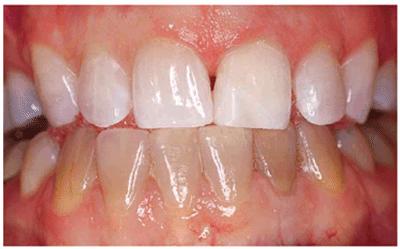

INTRINSIC STAINS

Much of the etiology of internal stains has been discussed in the first volume

of this textbook. Typically, bleaching with 10% carbamide peroxide in a

custom-fitted tray easily treats discolorations due to aging, smoking, or

chromogenic foods, and beverages (Figures 16-16A 16-16B 16-17A, and 16-17B). Although these types of stains

generally require only 2 to 6 weeks of bleaching treatment, some are more

Figure 16-16A: Some teeth darken over time from chromagenic foods. Some patients' teeth are just naturally yellow.

Figure 16-16B: Whitening of the maxillary teeth using 10% carbamide peroxide in a custom tray results in a more pleasing smile. This patient is now interested in closing the spaces.

Figure 16-17A: Some teeth darken through natural aging.

Figure 16-17B: Whitening of the maxillary teeth using 10% carbamide peroxide in a custom tray produces a normal progression of color from gingival to incisal edge but offers a more pleasing, younger look to the patient.